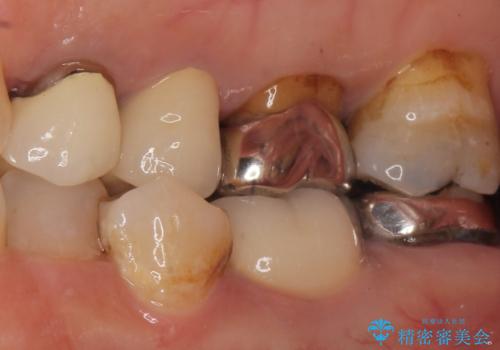

- 銀歯を白くしたいとご希望され、来院された患者様です。

他の歯科医院で銀歯をはずした時に、銀の詰め物が喉に飛んできたことがトラウマとなり、歯科治療が怖くなってしまったとのことでした。

患者様のご希望により、左上6クラウン、左上7インレーによるセラミック治療を行いました。